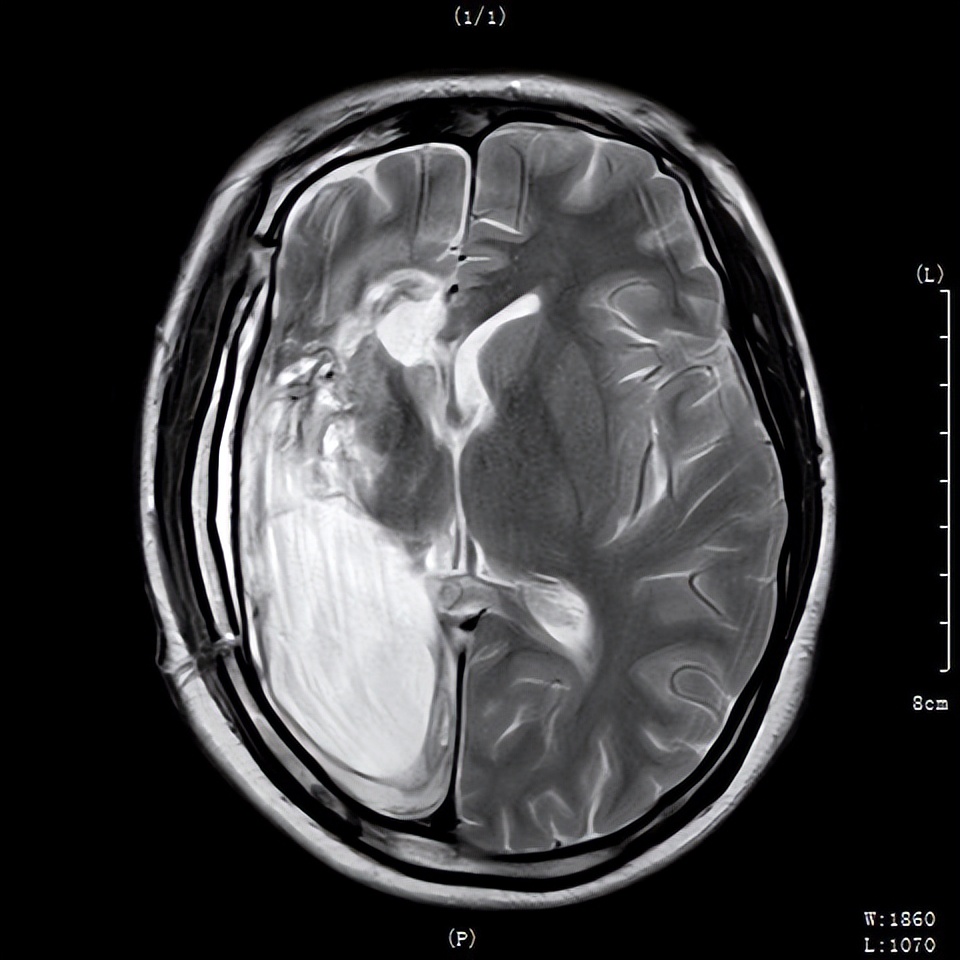

术前检查

完善脑电图检测、头颅核磁共振(MRI)、wada实验等全面检查后,脑电图结果提示:脑内存在癫痫样放电,且右侧大脑半球放电明显;MRI结果提示:右海马硬化,右侧大脑半球萎缩,考虑为致痫灶可能;wada试验结果提示:双侧肢体运动、语言、感觉等功能为左侧半球支配,考虑右侧大脑半球基本无功能,被左侧大脑带代偿。

结合检查结果,任副院长联合多学科专家会诊评估,认为娟娟符合大脑半球离断指征,最终为其制定了“右侧额颞开颅岛周大脑半球离断术”的治疗方案。